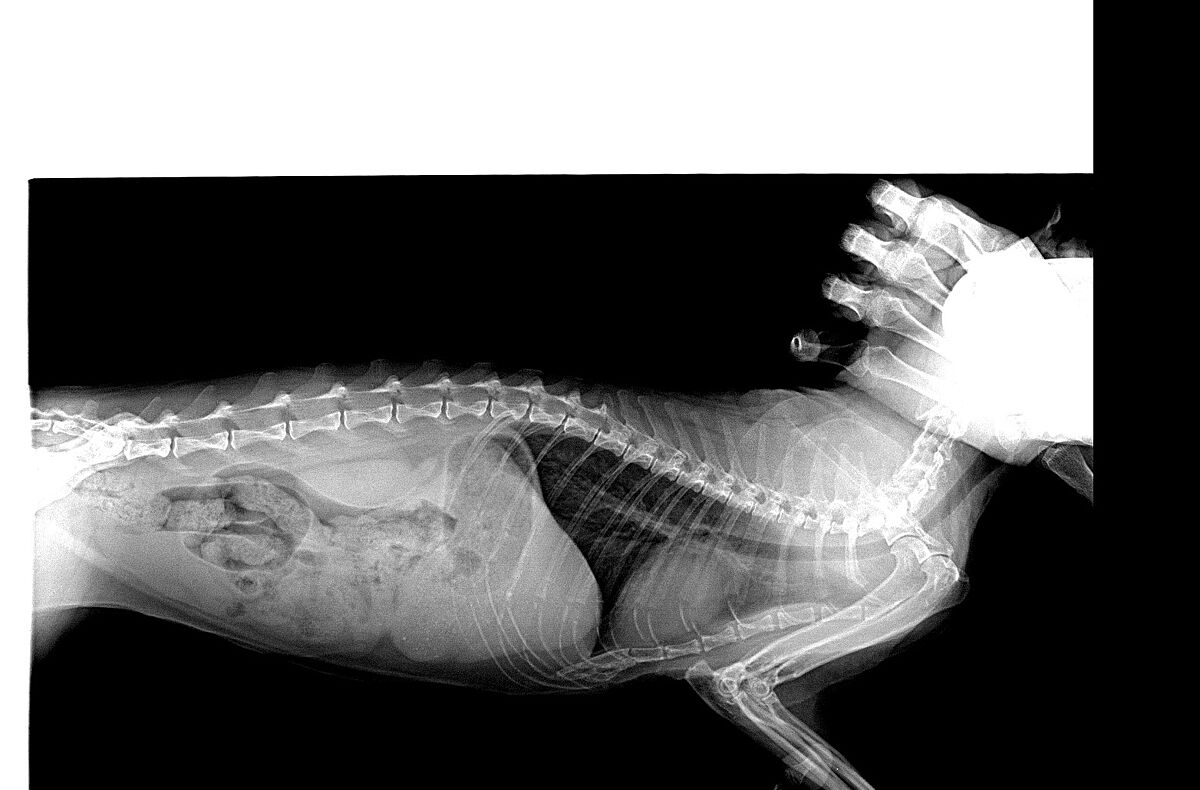

На Ваш взгляд по рентгену что это?

автор, вот как выглядит рентген у кошки у которой была частичная непроходимость из-за каловых масс, не ела 2 дня

может чем-то поможет..

меня смущает что у вашей большие легкие, сравните с моим снимком, (может реально отек), я сейчас поищу рентгены моих других кошек сделанные в другое время

у вас на скрине какие-то легкие буд-то вздуты, сходите еще к одному специалисту, какие еще есть симптомы?